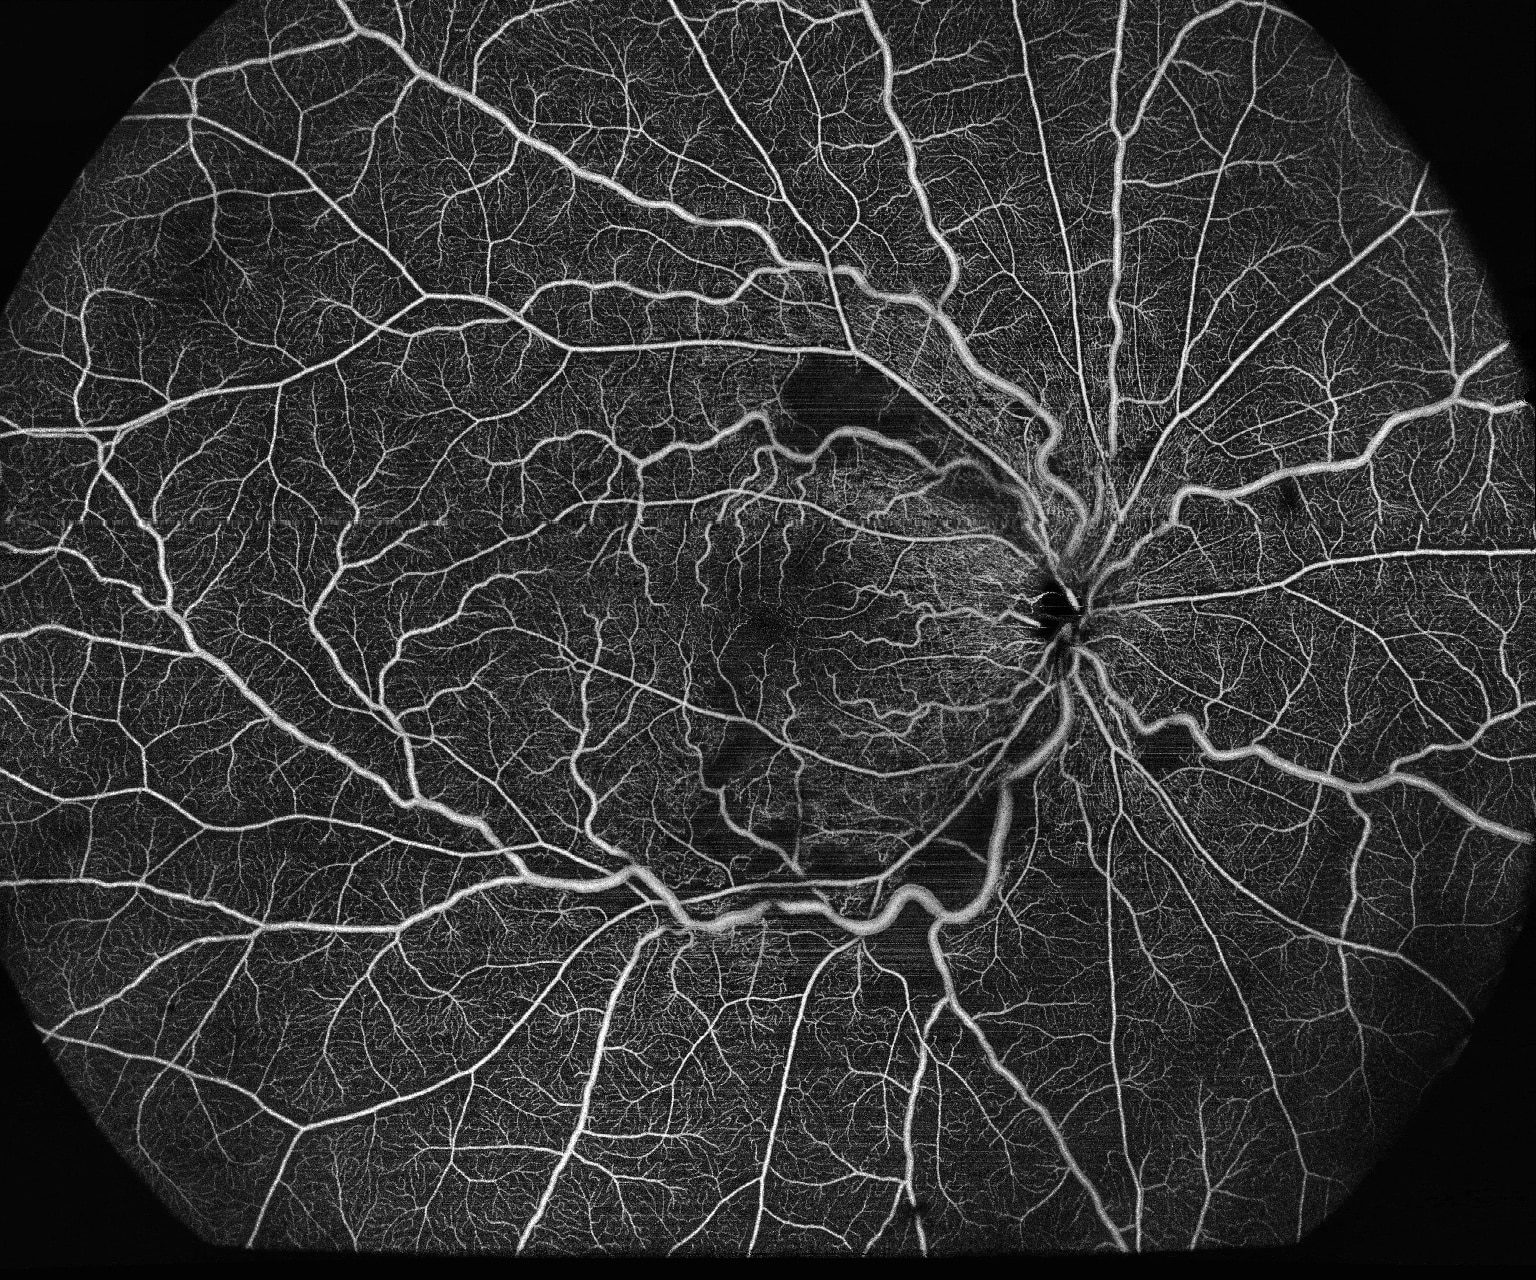

- Wide-field OCTA